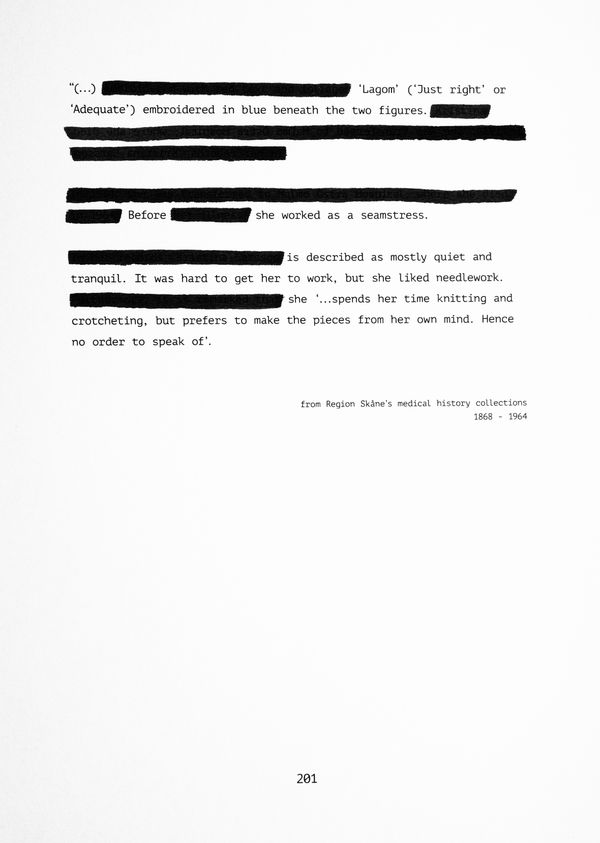

Inspired by the missing archive of her life's work, I began tracing other histories of women whose textiles speak where records fall silent, continuing the intergenerational legacy of weaving scraps into stories.

With the use of archival images and documents, staged compositions, and photographic interventions printed and layered through textile processes, the work is a reconstruction based on multiple (hi)stories stitched together: those of women makers, of rebels, and those whose voices were recorded, devalued, or lost.